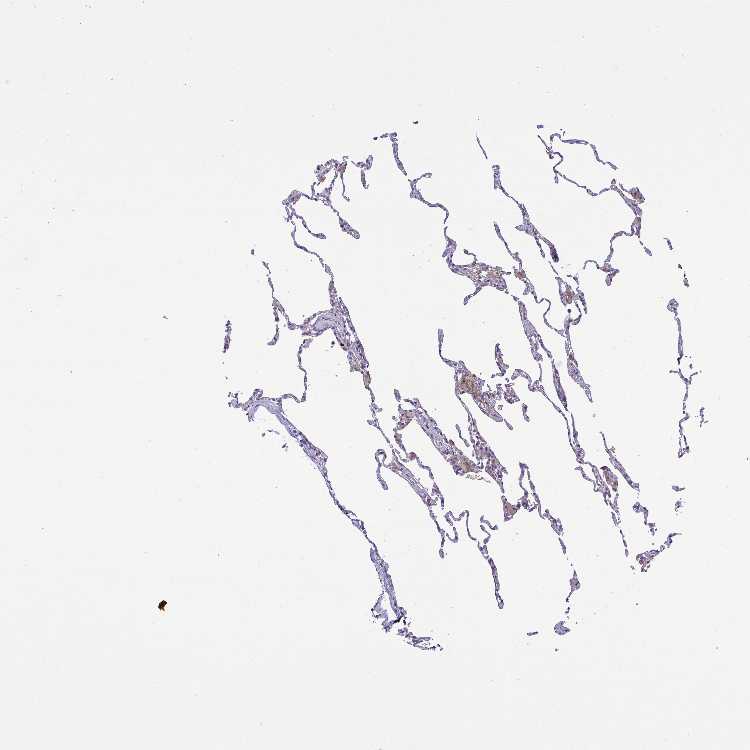

LUNG - Antibody stainingi

Antibody staining in the annotated cell types in the current human tissue is reported as not detected, low, medium, or high, based on conventional immunohistochemistry profiling in selected tissues. This score is based on the combination of the staining intensity and fraction of stained cells.

Each image is clickable and will lead to virtual microscopy that enables deeper exploration of all samples and also displays staining intensity scores, fraction scores and subcellular localization as well as patient and tissue information for each sample.

Antibody HPA057763

Alveolar cells Not detected

Macrophages Low